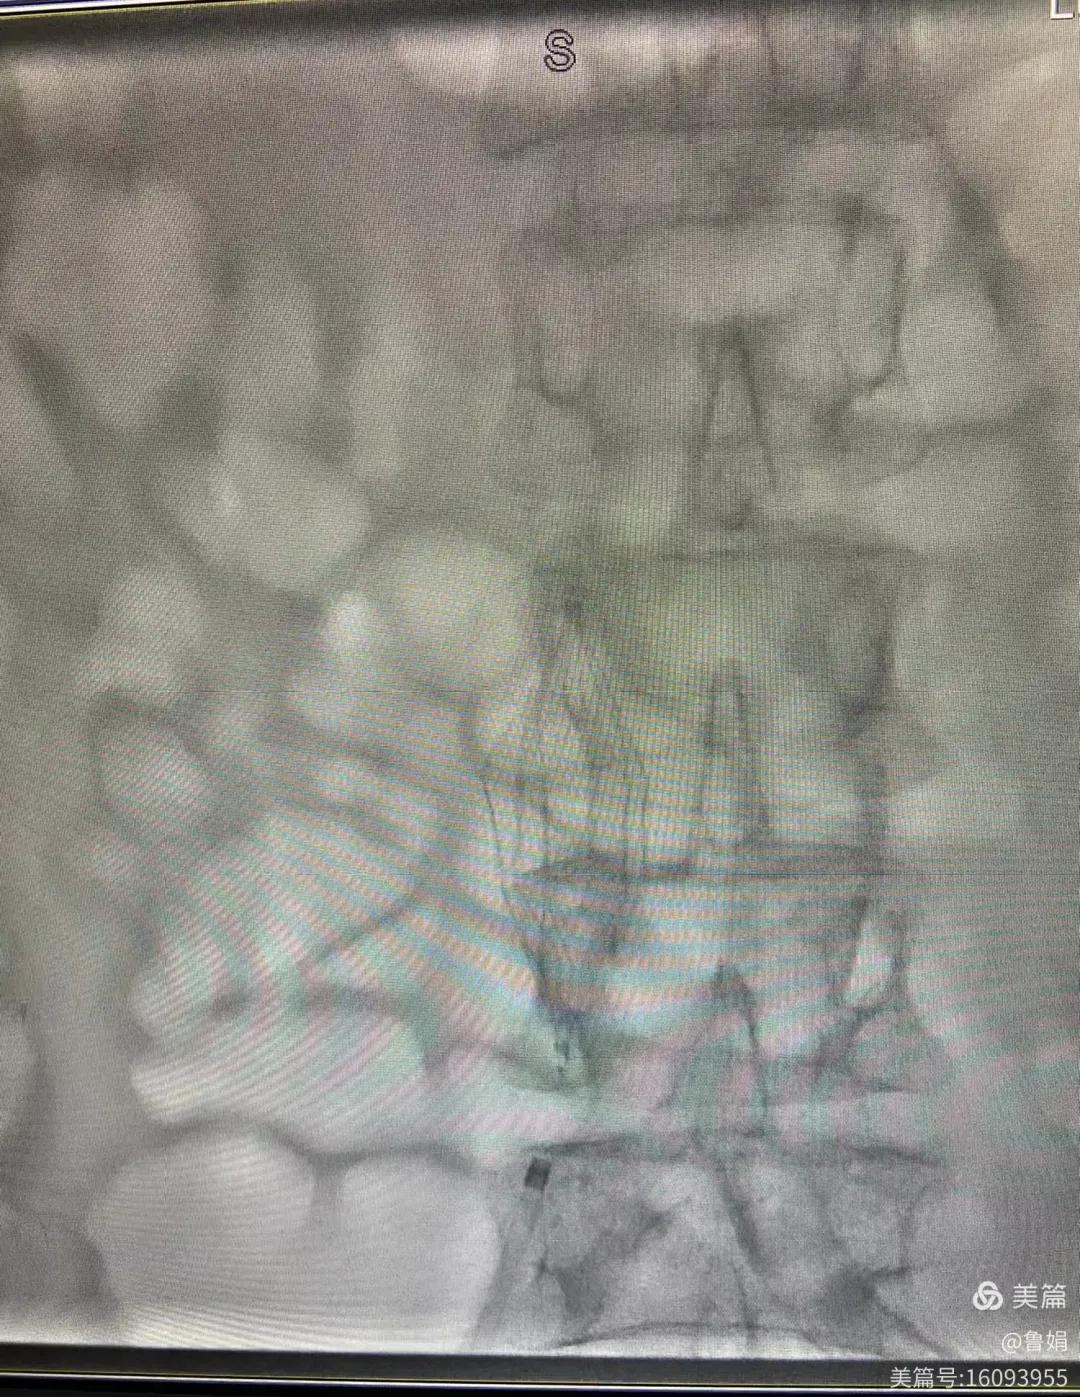

11月3日,漯河市中醫(yī)院血管外科副主任周創(chuàng)業(yè)與腦二科介入醫(yī)生孫亞中,兩位醫(yī)生為一位腦梗死伴下肢深靜脈血栓形成患者成功開展下腔靜脈濾器置入術(shù)。

圖片術(shù)后濾器順利植入

經(jīng)認(rèn)真查看患者病例,探討患者病情及術(shù)中潛在風(fēng)險(xiǎn)因素,多科會診后急診為患者開展介入手術(shù),術(shù)中周創(chuàng)業(yè)副主任、孫亞中副主任中醫(yī)師二人通力合作,手術(shù)順利,病人術(shù)中出血少,生命體征平穩(wěn),現(xiàn)在腦二科病房繼續(xù)對癥治療。(介入中心:魯娟)